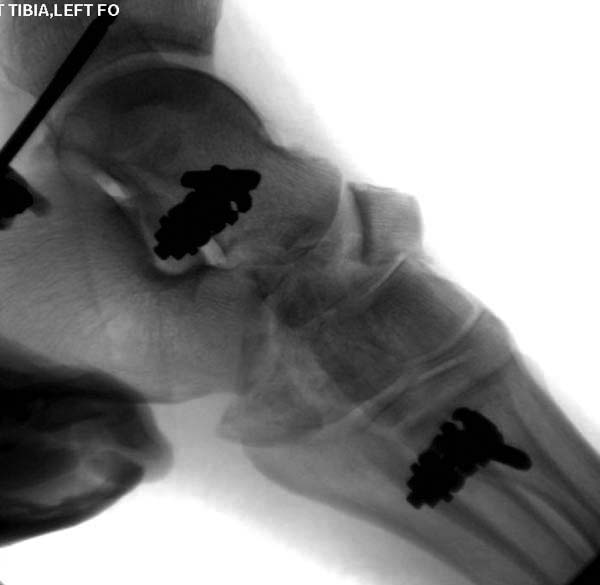

Современную тактику лечения переломов пилона описали коллеги, а мне остается подтвердить клинически. В многоэтапном лечении главное - это предупреждение сокращения мягких тканей, от которого зависит судьба конечности. Дистракция любым наружным фиксатором, и по готовности мягких тканей - премежуточная или окончательная фиксация.

В нашем случае, травма в результате коллапса крыши. Открытый перелом. Ургентные Irrigation and Debridment, дистракция наружным фиксатором. В госпиталях первого уровня редко бывает изолированная травма, и на другой стороне повреждение стопы с переломом навикулярной кости. После обработки раны - вакуум и двухсторонние наружные фиксаторы.

Через три дня повторная I&D, где через рану манипулировали дистальным фрагментом с установкой пары межфрагментарных шурупов. На рану вакуум и следующая обработка закончилась закрытием раны. Отек держался немного дольше, чем обычно.

После спадения отека вариантов фиксации много, включая мининвазивную технику, но данный случай закончили установкой простого аппарата Илизарова.

Через три дня оперирована стопа и для нейтрализации сил колонн оставили наружный фиксатор.